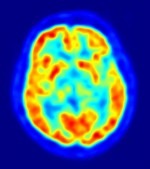

To really understand the mechanics of anxiety in SP terms, you first need to understand what happens inside the typical athlete’s mind. An athlete, who wants to overcome some mental block that is holding them back in their sport, needs to master two types of thoughts or thinking. The first is the cognitive or conscious mind thinking and the second is the automatic or unconscious mind.

The conscious mind makes changes very easily. If you give the athlete’s conscious mind some new ways of doing things that makes  sense and they believe it will improve his chances of performing better, they can easily adopt the new way of thinking and adopt the behaviors needed to make the changes happen.

On the other hand, the unconscious mind is not so easily swayed and can actually be quite stubborn. If you have ever experienced a mental block and tried to get “over” it, you know this is true.

The unconscious mind is like an elephant and the conscious mind is like the rider. An elephant can easily resist whatever the rider wants it to do, but if the rider and the elephant are in sync, then they are unstoppable and can achieve powerful goals together.

Typically SP does a good job of helping the conscious mind, the rider on top of the elephant. They help the athletes, like the rider of an elephant, give directions to the mind of the places they want it to go.

That works some of the time, unless the athlete’s unconscious mind has some mental block that will hold them back. In our mental toughness training, we dig deeper by teaching the athlete/rider how to communicate with the elephant to get it to go where they want it to go.

At Mental Toughness Academy, we help athletes discover how to tap into their unconscious performance nervous center! Have you ever heard a coach or commentator say about a brilliant performance: “He’s playing unconscious!” That’s what makes for amazing performances.

Athletes need to learn to tap into their EMOTIONS so they can communicate with their unconscious mind. The problem with many SP programs for athletes is they teach athletes to push down, ignore, or otherwise suppress their emotions thinking they will interfere with their performances.